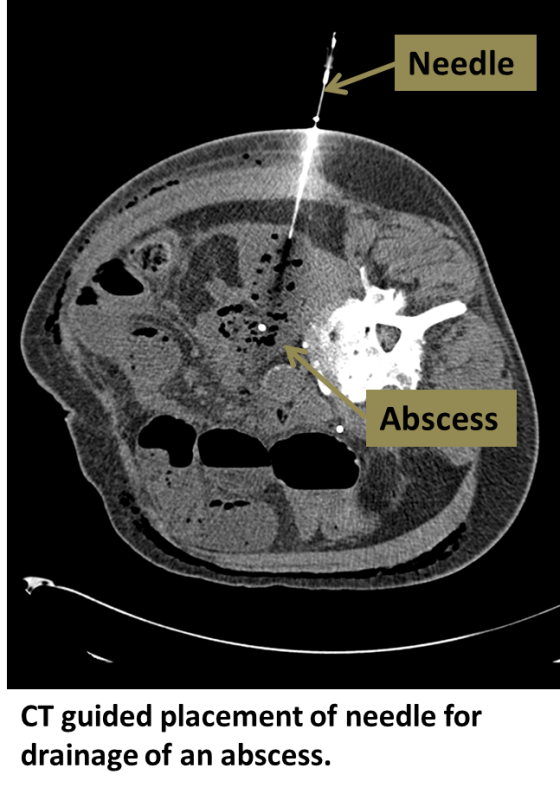

Interventional Radiology Drainage Procedures . Interventional radiology procedures in biopsy and drainage presents the full array of operations using these techniques. These fluid collections often require drainage for definitive treatment. In percutaneous abscess drainage, an interventional radiologist uses imaging guidance (ct, ultrasound or fluoroscopy) to place a thin. Placing a drain or catheter percutaneously under imaging guidance is an increasingly utilized medical procedure. An interventional radiologist uses ultrasound or ct guidance to place a drain into the abnormal.